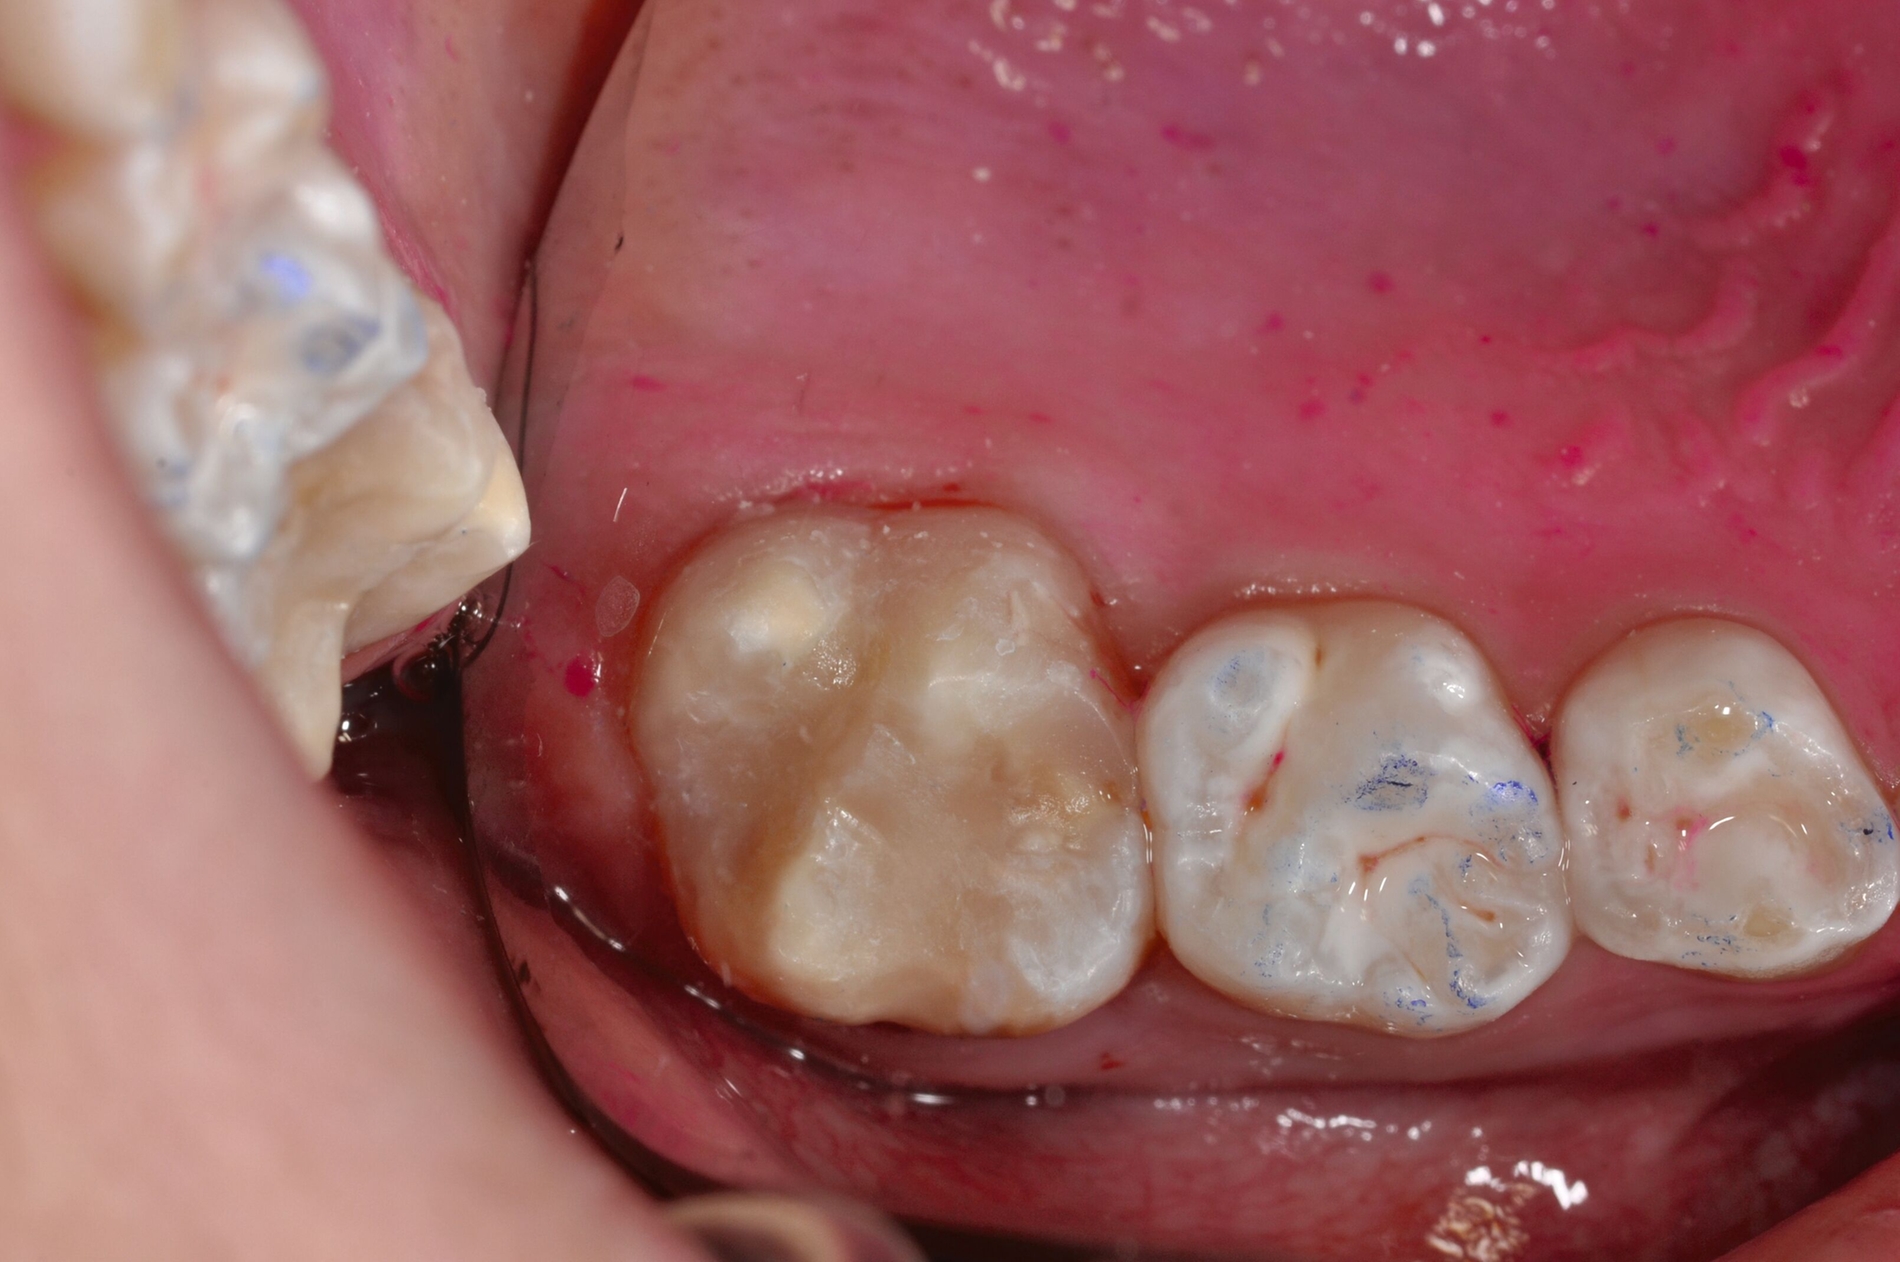

Die direkte Versorgung mit Komposit hat den Vorteil, dass durch die Verwendung von Dentinadhäsiven das Dentin dicht versiegelt werden kann. Hypersensitivitäten werden dadurch deutlich reduziert. Zudem kann der Zahn bei der direkten Versorgung sehr defektorientiert versorgt werden (Abbildung 7).

Während die Dentinhaftung unterhalb des affektierten Schmelzes vergleichbar mit der von gesundem Dentin ist, funktioniert die Haftung an dem strukturell veränderten Schmelz schlechter. Eigene Untersuchungen haben gezeigt, dass die Haftung an dem porösen, proteinreichen Schmelz stark reduziert ist (Abbildung 8) [Krämer et al., 2018]. Sind die Füllungsränder in dem veränderten Bereich lokalisiert, muss mit Randspalten und Abplatzungen gerechnet werden.

Bei größeren Restaurationen muss man im Laufe der Jahre mit Verfärbungen der Füllungen und mit Abrasionen rechnen. Dies spielt insbesondere eine Rolle, wenn im Seitenzahnbereich Höcker ersetzt werden müssen, da Kompositfüllungen mit Höckerersatz an MIH-Molaren eine etwas geringere durchschnittliche Überlebenszeit in der Mundhöhle haben als solche ohne Höckerrekonstruktion [Rolim et al., 2021].

Die Versorgung der MIH-Frontzähne entspricht dem Vorgehen im Seitenzahnbereich. Problematisch ist die Maskierung der Opazitäten. Dazu müssen opake Komposite verwendet werden und es muss eine Schichtstärke von circa 1,5 mm garantiert sein (Abbildung 9).